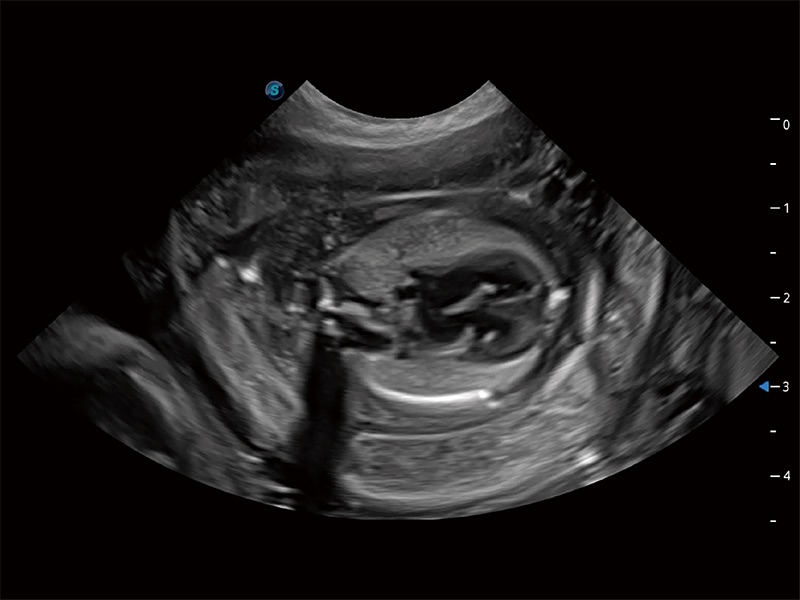

ProPet 80 配備了豐富的心臟探頭群、先進(jìn)的成像技術(shù)和專業(yè)的心臟測(cè)量工具,可幫助動(dòng)物醫(yī)生為不同體型和生理結(jié)構(gòu)的動(dòng)物提供心臟和心肌功能的全面評(píng)估。

ProPet 80 專為動(dòng)物醫(yī)生設(shè)計(jì),對(duì)不同的動(dòng)物體型和生理結(jié)構(gòu)作出了針對(duì)性的優(yōu)化。通過動(dòng)物影像專用軟件,可滿足個(gè)性化的應(yīng)用需求,幫助動(dòng)物醫(yī)生獲得更精確的診斷數(shù)據(jù)。

ProPet 80 全新的動(dòng)物超聲智能軟件和豐富的探頭群,為動(dòng)物醫(yī)生提供了高清晰度和精細(xì)分辨率的圖像,無論在寵物、馬科、畜牧還是實(shí)驗(yàn)室動(dòng)物等應(yīng)用中都可以輕松應(yīng)對(duì),為您的日常工作帶來滿意的體驗(yàn)。